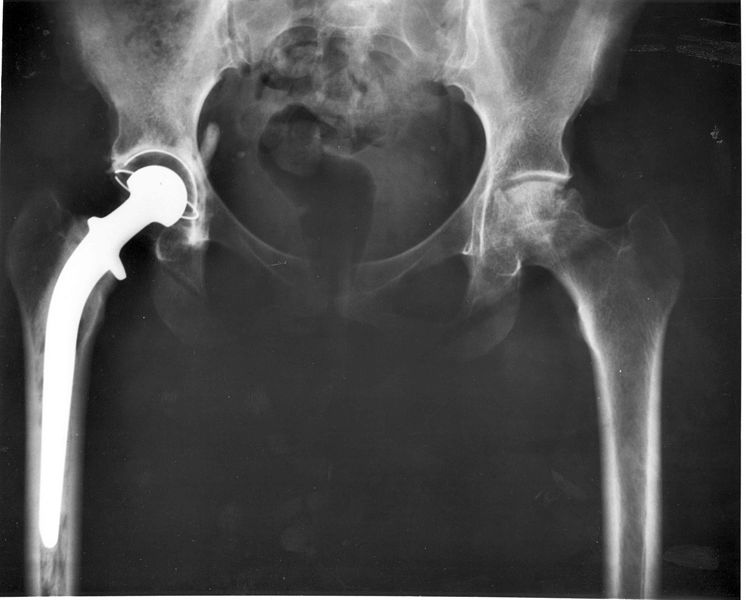

Tom's Physiotherapy Blog Surgery to the Hip

Tom's Physiotherapy Blog Surgery to the Hip Treatment For Hip Out Of Place  Usually, an orthopedist can simply push the ball back in by hand while the patient is under anesthesia. A hip dislocation is when the hip’s ball joint comes out of its socket. This is done as soon as possible to. Repositioning the thigh bone into the joint. Web  people who sustain a hip dislocation typically require sedation or general anesthesia. Treatment For Hip Out Of Place.